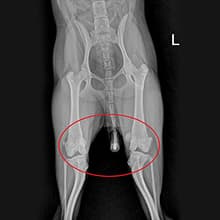

엑스레이2살 비숑프리제 : 슬개골탈구 수술

2살 비숑프리제가 옥길아라동물치료센터에 내원했습니다. 처음 내원할 때, 아이가 잘 걷지 않으려고 해서 병원에 내원해주신 경우입니다. 정확한 확인을 위해 정형 검사와 영상 검사를 진행하였습니다. 꼼꼼한 검사 결과 우측 슬개골 탈구3기와 좌측 슬개골 탈구 2기로 진단되었습니다. 엑스레이 검사 상으로 양측 슬개골이 내측으로 변위되었고, 우측의 변위가 더 심했습니다. 보행에 큰 불편함이 확인된 상태로 수술적 치료가 필요한 상황이었습니다. 수술은 증상에 따라 다른 수술 방법이 적용됩니다. 옥길아라동물의료센터 의료진은 정밀한 수술과 예후 관찰을 진행하였습니다. 양측 대퇴골 활차구 성형과 슬개골 탈구 3기에 해당하는 우측은 경골 조면 이식술을 병행 적용키로 결정하여 수술을 진행하였습니다. 수술 경험이 풍부한 외과 전담 선생님과 전문 의료진이 아이의 수술을 전담 진행하였고, 수술 후에는 빠른 회복을 재활치료를 진행해 주었습니다. 수술 후 2일차부터 염증 수치는 안정화되었고, 3일차 부터 잘 걷게 되어 무사히 보호자님께 인계되었습니다.